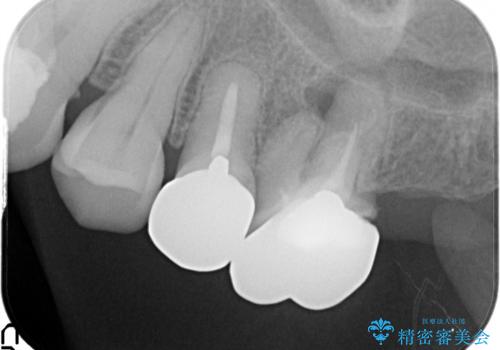

左側の上下の奥歯に適合が悪く、レントゲン上でも根の治療が必要なところがありました。

再治療を行いました。

根管治療からの再治療を行ったことにより、治療期間が多少長くなりましたが、今後再治療の必要性があまりないような、精度の高い治療ができました。